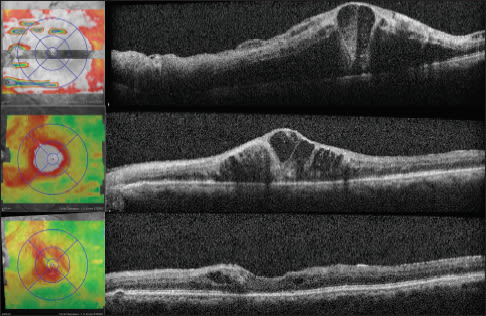

Case 3: A Stitch in Time. A 73-year-old male was referred in May 2010 by an outside retina specialist for treatment of CRVO in both eyes. The right CRVO had occurred in February 2010 and had received two previous bevacizumab injections, and the left CRVO had occurred in April 2010 and had received one bevacizumab injection. On presentation, VA was 20/100 in both eyes, and the examination showed findings consistent with the presenting diagnosis, with SD-OCT confirming CME in the right eye and a relatively compact retina in the left eye (Figures 4 and 5, top) Especially because of the subjective and objective visual acuity, the patient subsequently received subsequent bilateral bevacizumab injections over the next two months. In July 2010, the visual acuity was 20/60 in the right eye and 20/50 in the left eye. The SD-OCT appearance (Figures 4 and 5, middle) demonstrated persistent CME in the right eye, and the same compact appearance to the left macula. Because of the visual improvement and lack of obvious CME on SD-OCT, treatment was deferred for the left eye, though continued for the right eye.

Figure 4. Case 3: A 73-year-old male with bilateral CRVO and CME. SD-OCT shows CME in the right eye (top) with a VA of 20/70. After two injections of Avastin, there was less subretinal fluid (middle) and VA was 20/60. After continued treatment, there was persistent CME and VA was still 20/60. However, after three more injections, the CME decreased, and VA was 20/40.

Figure 5. Case 3: SD OCT shows a relatively compact retina in the left eye (top) with a visual acuity of 20/70, and a similar appearance after two intravitreal injections of Avastin (middle) although a VA of 20/50. Treatment was then deferred, but one month later CME reaccumulated and VA dropped to 20/100 (bottom). After continued treatment, the CME decreased and VA was 20/50.

Four weeks later, the patient returned with a visual acuity of 20/60 in the right eye and 20/100 in the left eye, and SD-OCT demonstrating persistent CME in the right eye and new intraretinal fluid in the left eye (Figures 4 and 5, bottom). Bilateral intravitreal bevacizumab injections were performed, and continued monthly until most recent follow-up in March, 2011, when visual acuity was 20/40 in the right eye and 20/60 in the left eye. Bilateral intravitreal bevacizumab injections were performed and were continued monthly until the most recent follow-up in March 2011, when the patient's VA was 20/40 in the right eye and 20/60 in the left eye.

This case illustrates that as-needed dosing, based on visual stability and OCT retinal thickness, may be initially detrimental to VA and may potentiate a longer duration of visual recovery. On the most recent follow-up, this patient had not yet regained the VA originally achieved after consecutive, initial monthly injections in the right eye after just a single month's break. In contrast, the left eye had continued to gain ground and allowed the patient to return to the level needed for legal driving privileges.